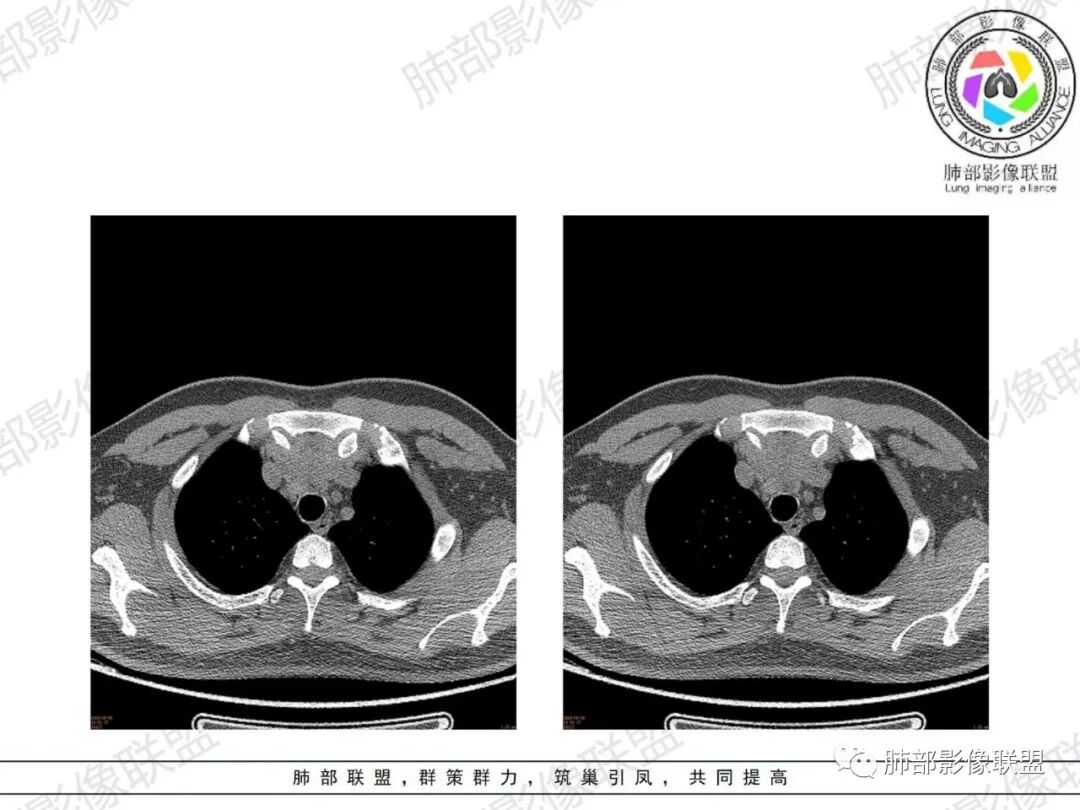

南边分析-征象标注

年轻男性,双下肌乏力,可惜没交代是啥手术,是不是前纵隔病变手术。

1、一般这样的乏力:1.神经系统问题;2.胸腺问题。

* 整个形态就是胸腺的形态,定位在前纵隔,胸腺病变应该可以。26岁男性,这么年轻,胸腺源性肿瘤几率比较低,

1.非肿瘤性病变2.其他来源肿瘤性病变

2、下半部分,形态自然,边缘稍膨隆,内部密度实性夹杂稍低密度影,而且是线样低密度影,比较自然走形,支持胸腺组织增生或残留。如果其他肿瘤所致,应该是边缘膨隆,类圆形,内部密度均匀,或部分区域坏死,或者结节状灶之间间隔。所以这个首先:胸腺增生或残留应该有。

* 部分区域边缘平直、稍凹陷,部分密度较低,边缘稍膨隆。

* 部分密实。因为没有增强,附近血管分不开,内部密度差不是那么明显,但是有密度差。提示:内部组织结构有变化,不是单一的组织结构。

考虑:1.发生过炎症或内部组织增生程度不一,导致各区域密度差

2.不除外合并其他病变:

①可能合并囊变

②目前的资料不能排除合并其他肿瘤性病变的可能性

1、年轻男性,双下肌乏力,胸部CT提示前纵隔胸腺区病变,应当怀疑胸腺增生或胸腺瘤导致的重症肌无力。

2、前纵隔梨形软组织密度影,与正常胸腺形态一致,为胸腺弥漫性增大,两缘匀称,质地柔软,未见明显膨隆,其内可见脂肪浸润影,与周围结构分界清楚,再加上病人年龄,需要高度提示胸腺增生(淋巴滤泡样增生型)。胸腺瘤一般无脂肪浸润,质地较硬,呈结节或肿块状,且发病年龄较大。B2B3型肿块边界不清,可侵犯临近组织脏器,B3可胸膜转移,胸腺癌可引起纵隔淋巴结及远处转移。